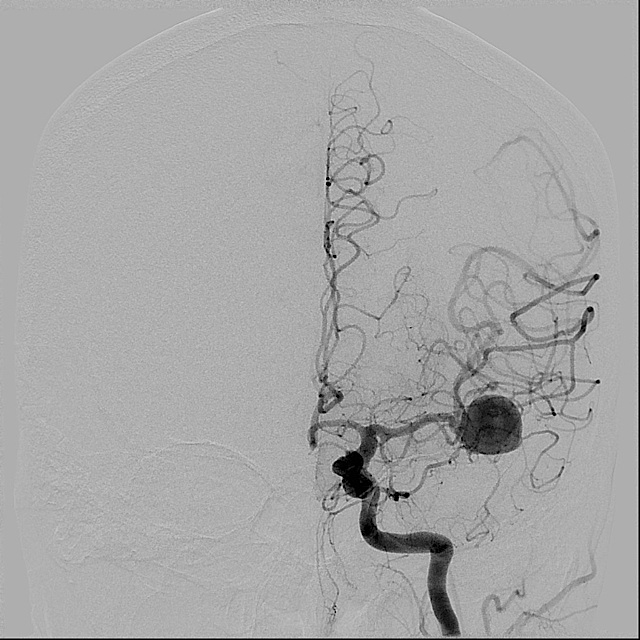

Cerebral angiography was then performed demonstrating the left MCA aneurysm. Aneurysm was measured in Image 6.

| Image 4 - Cerebral Angiogram | Image 5 - Cerebral Angiogram | Image 6 - Measurements |